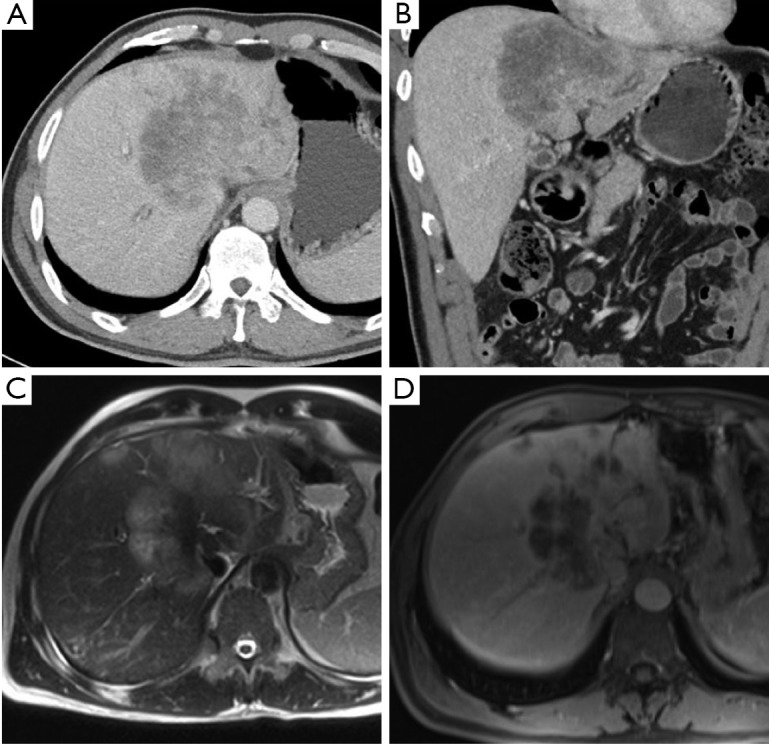

- Tomografia computerizzata (TC): la TC multidetettore con mezzo di contrasto è la modalità più utilizzata per la stadiazione e la valutazione della resecabilità, con un’accuratezza riportata tra il 60% e il 90%. Le scansioni in fase arteriosa e portale sono essenziali per delineare con precisione l’invasione dell’arteria epatica e della vena porta. I limiti della TC risiedono nella sua minore accuratezza nella valutazione del coinvolgimento linfonodale e nella rilevazione di piccole metastasi peritoneali.

- Risonanza Magnetica (RM) e colangiopancreatografia a risonanza magnetica (CPRM): queste tecniche stanno guadagnando sempre più favore. La RM offre un’eccellente risoluzione di contrasto dei tessuti molli, mentre la CPRM fornisce una visualizzazione non invasiva e dettagliata dell’albero biliare, paragonabile alla colangiografia diretta. La combinazione di RM e CPRM ha un’accuratezza di circa l’80% nel predire la resecabilità ed è particolarmente vantaggiosa per la stadiazione biliare, definendo l’estensione del tumore lungo i dotti.